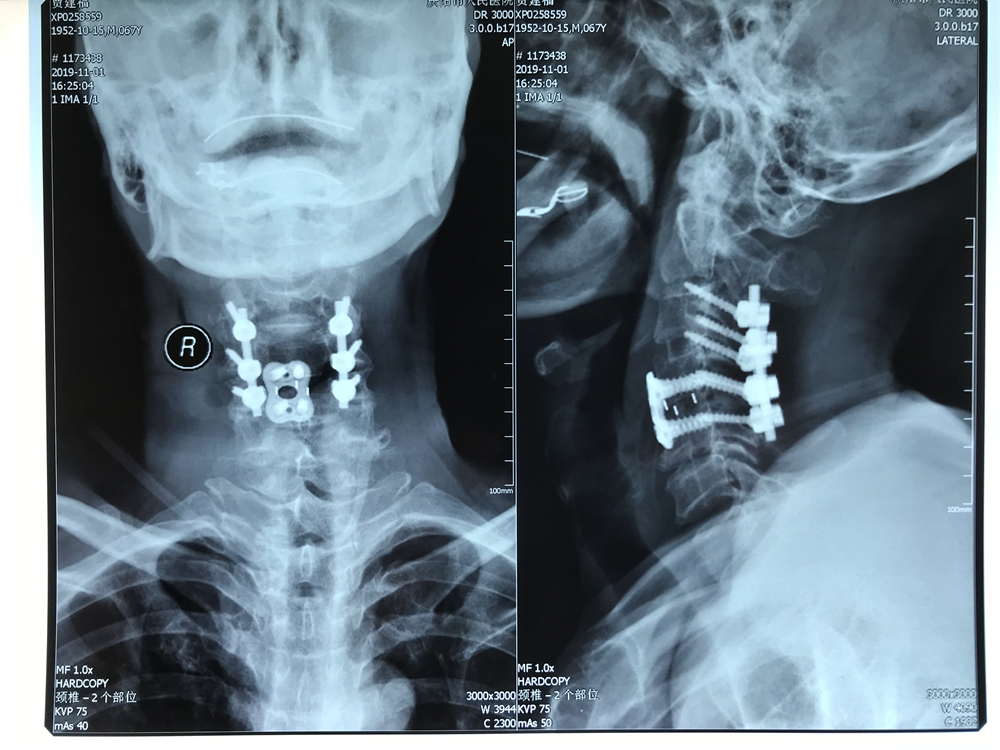

患者67岁,男性,在家劳作时不慎从高处摔下,头部落地,致颈部受伤,受伤当时即感觉颈部疼痛并有双上肢麻木、活动受限,被家属紧急送往当地医院就诊,相关检查后明确诊断:颈4椎体完全性滑脱并颈5椎体骨折。因手术难度高,患者随即转诊至我院骨一科就诊。科室迅速组建救治团队,经过缜密的术前讨论,决定首先行颅骨牵引手术,缓解患者神经受压症状,随后根据患者情况细化手术方案——决定全麻下为患者一期行颈椎前后联合入路切开减压、脊髓探查、椎体滑脱复位内固定手术治疗。

在骨一科医护团队及麻醉手术配合下,手术历时4小时,患者转危为安。经过康复训练,患者出院时可以自主下床活动、自主进食及解大小便,生活质量得到保证。

此例手术是我市骨科成功实施的首例一期完成颈前后联合入路颈椎椎体完全性滑脱并椎体骨折内固定术。该患者骨折的部位属于高位脊髓水平,紧邻呼吸循环等生命中枢,手术中稍有不慎,就会引起高位肢体瘫痪甚至死亡,过去往往被认为是“手术的禁区”。此类患者多数在受伤当时即出现危及生命的严重损伤,现场死亡率高,手术处理较为棘手,一般出现在严重车祸伤、高处坠落伤等情况下,要完成此类高难度、高风险的手术,要求手术团队有专业的理论知识、完善的术前准备和精准的手术操作。此例手术的成功,标志着我院骨一科脊柱外科事业发展步入了一个新的台阶。